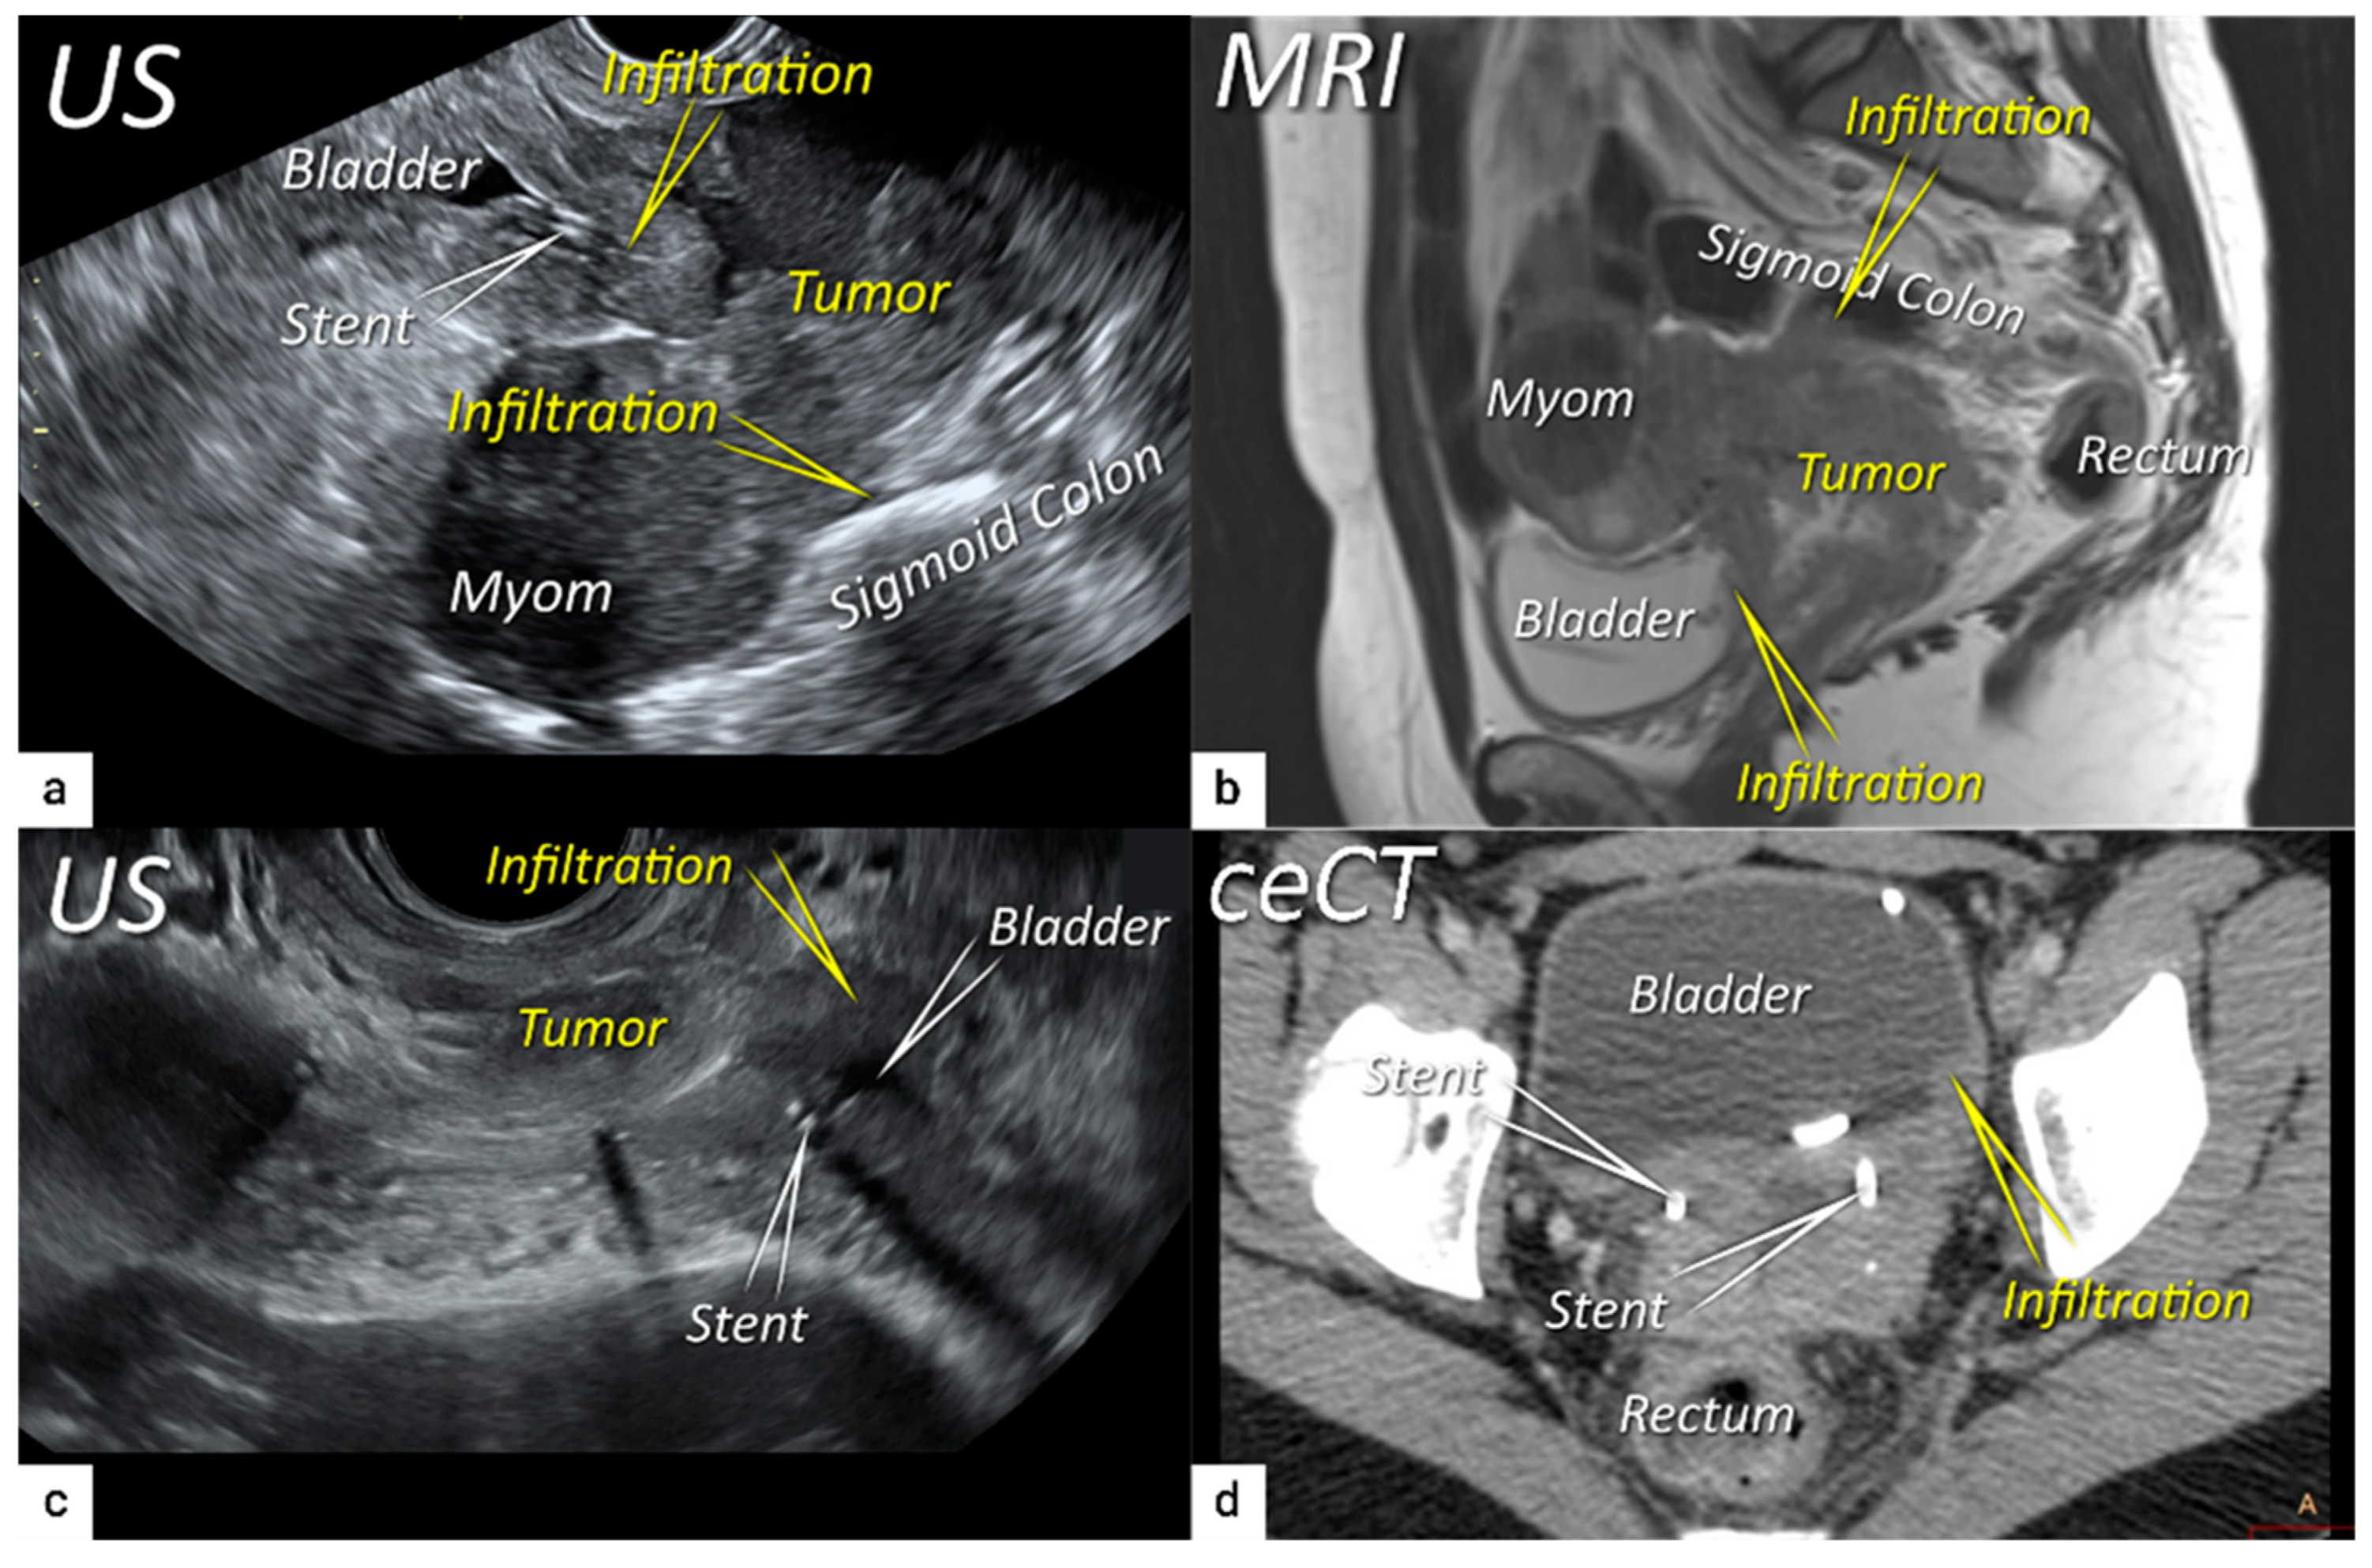

3.4. Extension to Surrounding Organs (Bladder, Rectum, Sigmoid Colon)

| T4 f | IVA f | Tumour invasion into the mucosa of the bladder or rectum (biopsy-proven) or into adjacent organs. | Tumour invasion into the mucosa of the bladder or rectum on imaging, confirmed by biopsy. US: Negative sliding sign, hypoechogenic tumour infiltration of bladder/rectal wall up to echogenic mucosa with polypoid tumour seen intraluminally. MRI: Focal or diffuse disruption of the normal T2-low signal intensity wall of the bladder/rectum, irregular or nodular wall, sometimes including an intraluminal tumour mass. Bulous edema sign, which is hyperintense thickening of the bladder mucosa on T2W images, is only an indirect sign of invasion and should not be regarded as T4 unless confirmed mucosal infiltration at cystoscopy. Infiltration of the posterior bladder wall without mucosal infiltration should not be regarded as T4a. |